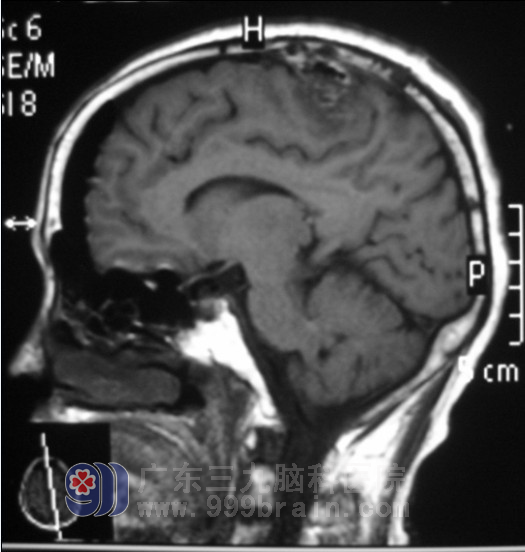

入院后,完善相关检查,头颅MR检查示“左顶部占位,直径约3cm,考虑脑膜瘤可能”。初步诊断:左顶叶占位病变(脑膜瘤可能性大)。广东三九脑科医院神经外五科 鲁明主任查看后,凭借着多年的临床经验,指示完善术前相关检查,择期手术治疗。入院第五天鲁明主任为张阿姨在全麻下行“左侧额顶镰窦旁脑膜瘤切除术”。术中见肿瘤明显侵犯硬膜,并部分侵犯上矢状窦,肿瘤质中,灰白色,边界清,予显微镜下连同受侵犯硬膜一起完整切除,术后予以抗炎止血等治疗。术后随访:张阿姨身体恢复得很好,头晕症状消失了。”http://www.999brain.com

▲术后